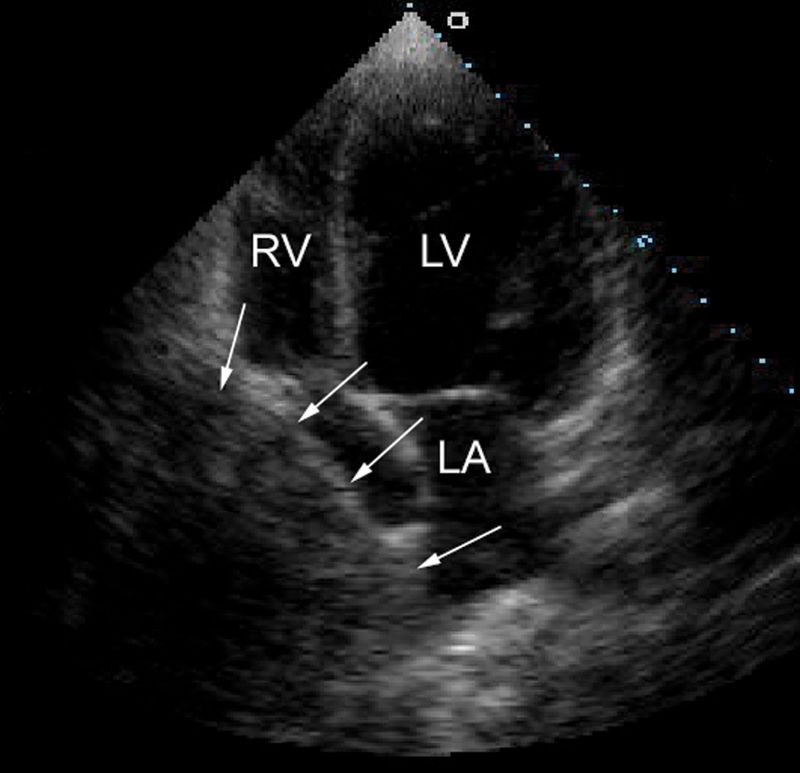

فحوصات تشخيصية لبعض امراض القلب والشرايين التاجية